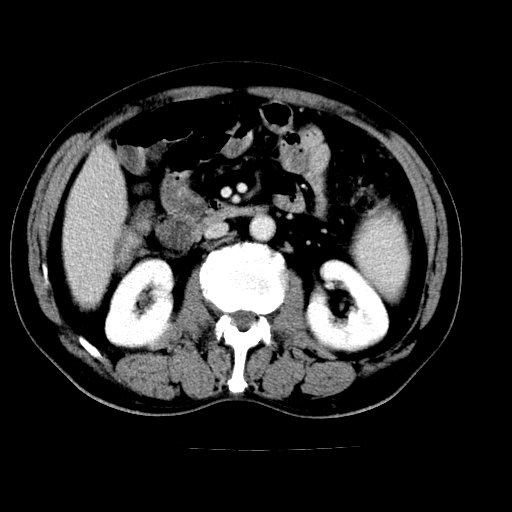

男,66岁,上腹部不适、黄染一周。彩超示:肝左叶占位,肝内胆管扩张,胆总管扩张,胆总管占位?

肝左叶占位性病变,并胆管扩张,符合胆管细胞癌ct表现,门脉左支受累,左肾囊肿。窗宽太窄了,其他的看不清

左叶胆管细胞癌累及胆总管,门脉左支受侵,慢性胆囊炎胆结石,左肾小囊肿

支持肝左叶肝内胆管细胞癌伴胆总管及门脉左支受侵。